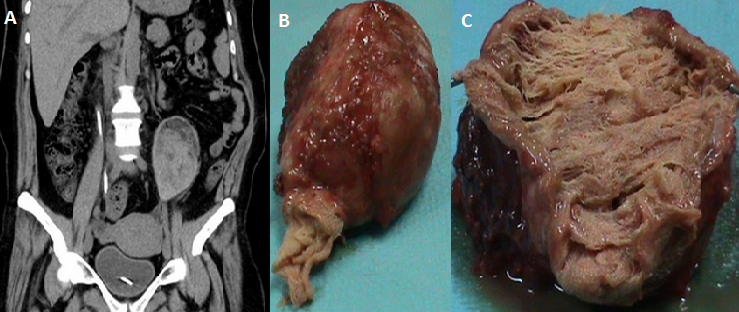

A 47-year-old woman with a history of nephrolithiasis complicated by chronic renal failure presented with recurrent left flank pain. Nine months ago, she had been subject to an open surgery for left kidney pyonephrosis. She described a short febrile post-operative period; however, there had been no fever for the last eight months. On physical examination, she was afebrile and had a palpable tender mass in the left flank to suggest malignancy. Unenhanced abdominal CT showed a well-encapsulated ovoid heterogeneous mass, located within the left lumbar region (A). The mass resection was done (B). The patient tolerated the procedure and the postoperative period was uncomplicated. Since pathological examination showed retained surgical sponges surrounded by fibrous capsule as foreign body reaction (C), gossypiboma was diagnosed. A gossypiboma refers to a cotton-based foreign body left inadvertently in the human body following a surgical procedure. Gossypiboma is an uncommon condition, diagnosed preoperatively in only one third of all cases. New-onset or a recurrent tumor is the most common differential diagnosis. Gossypiboma should be considered in any postoperative patient presenting with pain, infection, or a palpable mass, particularly in countries where strict surgical protocols may not be in place.